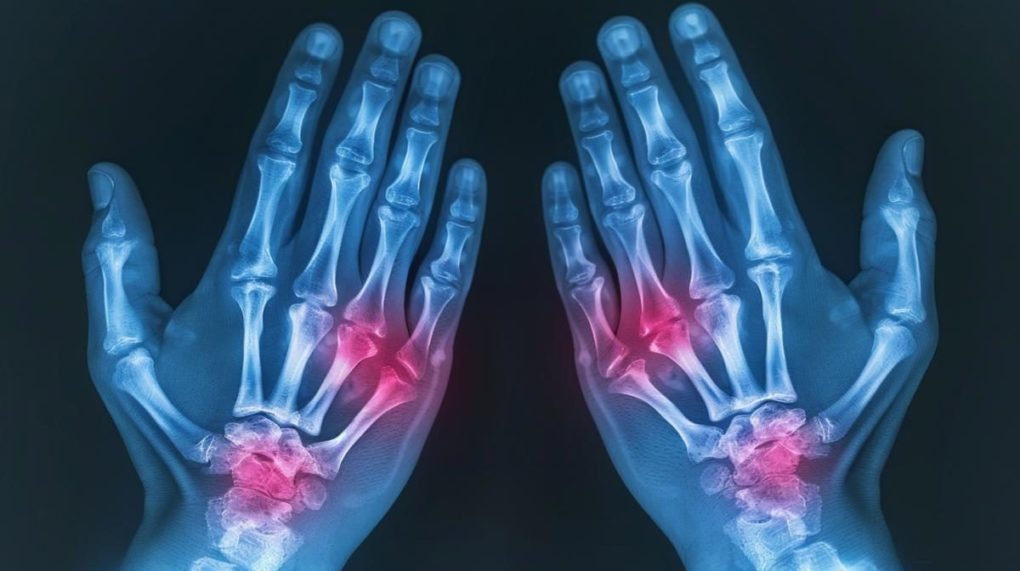

С ревматоидным артритом я впервые столкнулся в конце 2015 года. Мы вместе вот уже 10 лет, и это весьма солидный срок, ведь, к примеру, с женой мы пару месяцев назад отметили всего лишь пятую годовщину свадьбы. Сегодня мне есть, что вам рассказать – как за эту десятилетку менялось мое отношение к болезни, при чем тут вера, за что можно любить свою болезнь и быть ей благодарным, и каково это – быть 36-летним безработным инвалидом.

В самом начале, когда мне только поставили диагноз, я даже не подозревал о том, насколько это серьезное и паршивое заболевание. В силу своего юношеского максимализма, я вообще не воспринимал это за болезнь, почему-то полагая, что оно исчезнет так же внезапно, как и появилось. Не исчезло. Наоборот, с каждым годом, с каждым прожитым днем, оно все сильнее набирало обороты. Потом случился ковид, который придал течению болезни стремительное ускорение, а также отсутствие возможности принимать необходимые препараты ввиду планирования беременности. В какой-то момент болезнь стала потихоньку «пожирать» мое тело, пока я не оказался прикованным к постели в агонии нестерпимой боли.